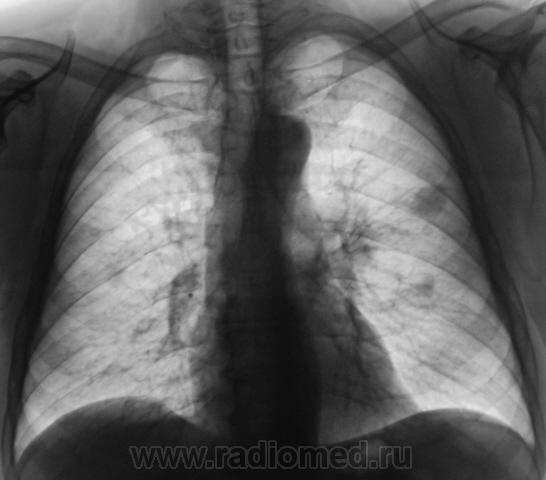

Пациент "взят на контроль" при расшифровке цифровых флюорограмм, дообследован - рентгенография в стандартных проекциях. Ваше мнение коллеги?

Произведены томограммы.

Пахнет периферическим c-r SIII лев. л-го, хотя на ТМГ он не получил должного отображения. Mts в лимфатич. узлы корня. Очаговые тени в легких вроде как связаны с сосудами...

MTS в правое и левое лёгкие, лимфатические узлы левого корня.